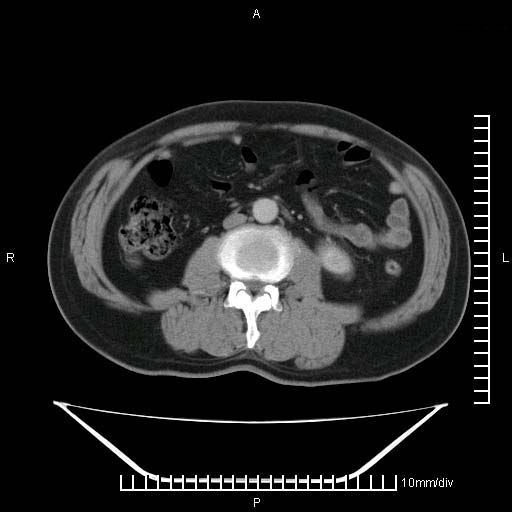

标题: CT25082:肝脏增强:男性,70岁 [打印本页]

标题: CT25082:肝脏增强:男性,70岁

患者以心脏疾病收住院,腹部无明显症状,b超查肝脏有占位。

牛眼征,中心坏死无强化,外缘强化,最外缘又见低密度,考虑转移,与脓肿鉴别

肝内多发转移瘤,右下肺炎症并少量胸水。胃壁增厚建议胃镜,胰尾部“病变”为肠管。

1)肝脏多发性转移瘤(不排除胰尾癌转移所致可能)。2)腹水。3)右侧少量胸腔积液。

ct25082 结果:转移瘤

外院mr结果:胰尾恶性占位。